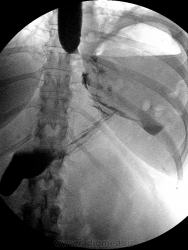

Буквально за час до окончания моего рабочего дня, хирурги к нам в отделение направили пациентку в состояние средней степени тяжести, для проведения R-скопии пищевода по Citо на предмет не состоятельности швов и затеков. Пациентке была проведено лапаротомия и фундопликация, но на 5е сутки появились значительные боли в животе, более выражены  в эпигастрии. Данной пациентке я проводил уже скопию пищевода с указанием на наличие  фиксированной грыжи пищеводного отверстия диафрагмы. Снимки до оперативного вмешательства:

а вот снимки уже сегодня сделанные:

Возможно полное впечатление об осложнении проведенного оперативного вмешательства сложиться после проведенной обзорной рентгенограммы органов грудной полости:

При избыточной фундопликации такое довольно часто, иногда проходит....   Сейчас еще и парез желудка, с приподнятостью диафрагмы, дисковидными ателектазами в легком слева... А не утаили ли от нас ваготомию? Парез часто после неё...

Стало быть затек в субкардиальном отделе по малой кривизне Вы полностью исключаете, Анатолий Владимирович?

Все намного сложнее в данном случае, как такого пареза на самом деле нет, общую картину преоткрывает "обзорка", на самом деле я сомневался по поводу заключения, но с учетом того что, её взяли на релапоротомию, надо обратить внимание на кардию желудка.

Мне кажется, что как раз большого криминала в наличие там воздуха нет (ведь вмешательтво было торако-абдоминальным), а вот мазок контраста в субкардии - это очень тревожно в плане несостоятельности.

Все это раздутый газовый пузырь на самом деле, контраст с трудом  стекает в с/3 желудка

Вы правы Виктор Григорьевич, есть затек, сегодня разговаривал с хирургами, вот что они увидели во время операции:В брюшной полости до 1 литра мутного серозно-гнойного выпота с резким ихорозным запахом. Петли тонкой кишки не расширены, не перистальтируют, единичные налеты фибрина. Стенка желудка, пищевод, большой сальник в зоне ранее выполненной операции инфильтрированы, плотные налеты фибрина на диафрагмальной поверхности селезенки, левом куполе диафрагмы. Брюшная полость осушена. Сняты два шва с ножек диафрагмы - поступления гноя из средостения нет. Желудок наполнен окрашенным физиологическим раствором - поступление последнего в брюшную полость не определяется. Выполнена интраоперационная ФГДС - поступление воздуха из области желудочной манжетки по левому краю пищевода. С учетом того, что именно в этой области пищевод ушивался во время первой операции, причиной гнойника является несостоятельность швов на пищеводе. Диагноз и тактика согласованы. Брюшная полость промыта 8 литрами физиологического раствора, осушена. Проведен зонд в тонкую кишку для последующего энтерального питания. Установлены дренажи в малый таз, двухпросветные дренажи(3) в подпеченочное и левое поддиафрагмальное пространство, тампон в подпеченочное пространство. Сформирована гастростома для декомпрессии желудка и предупреждения рефлюкса желудочного содержимого в пищевод.